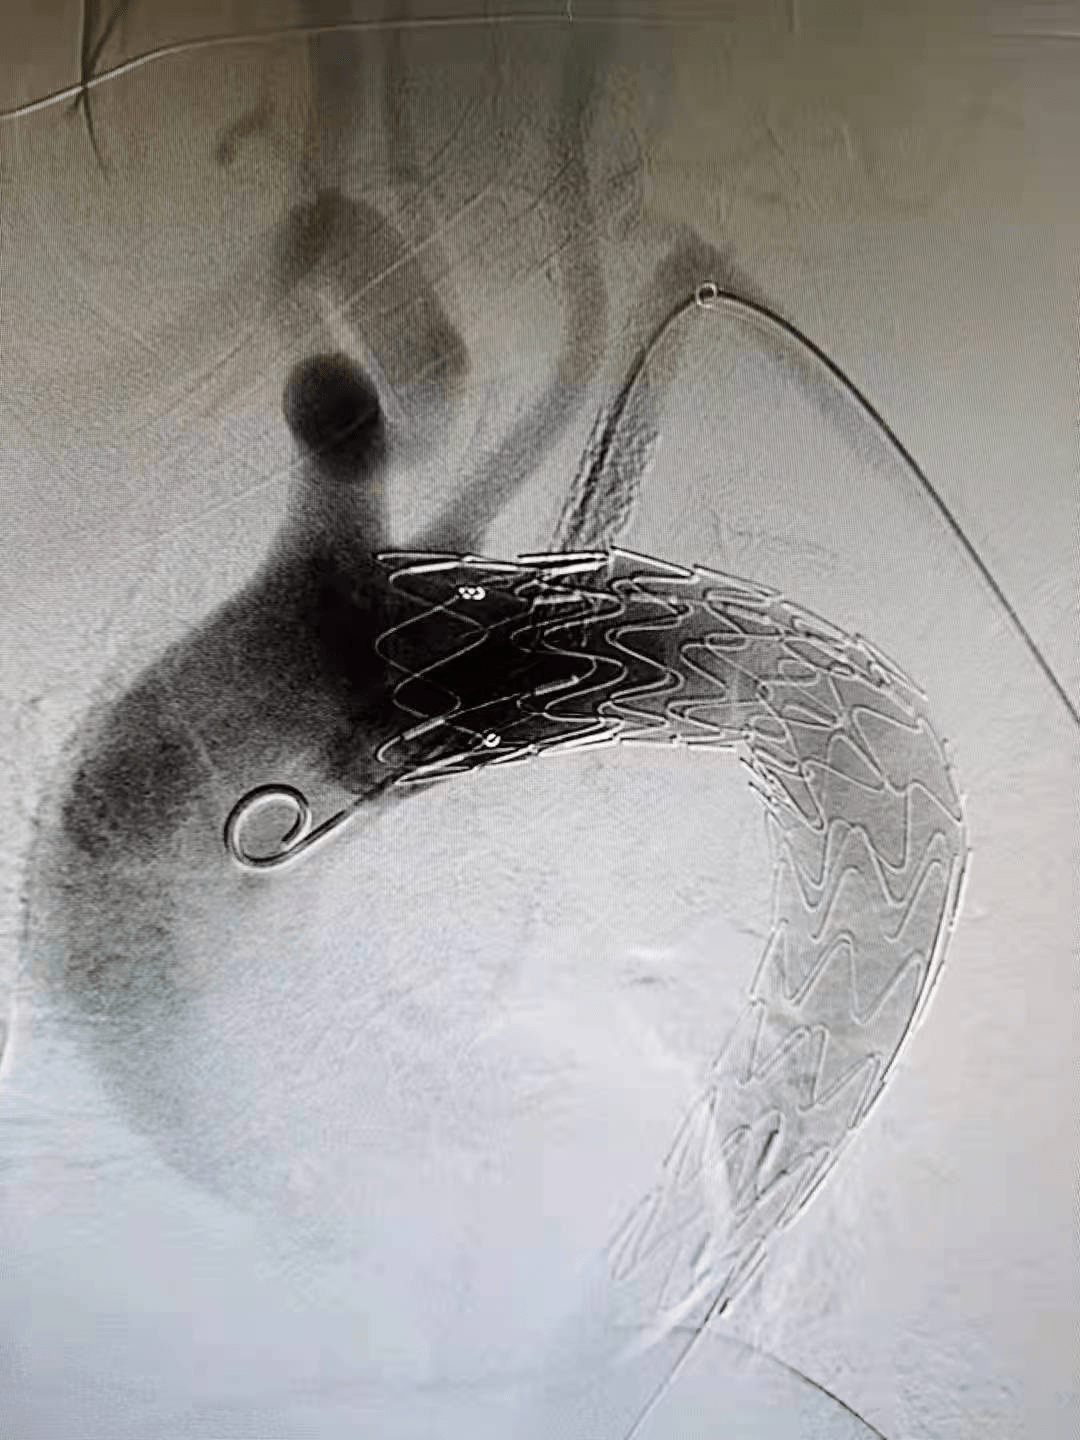

该院血管病诊疗中心专家组经过反复研讨 , 一致决定采用国际上最先进的技术“主动脉覆膜支架腔内隔绝+左锁骨下动脉体内原位开窗、球扩覆膜支架成形术”的手术方案 。 采用这种术式 , 既能彻底封闭溃疡 , 堵住出现的小“坑” , 又能保证左上肢和左椎动脉供血 , 恢复正常解剖形态 。

在介入手术室王素娟护士长和付晓慧、陈浩等护士积极配合下 , 刘洪主任带领潘仲杰和郑鹏远两位医生 , 沿患者右侧股总动脉造影(见图二、图三)置入胸主动脉覆膜支架 , 于左颈总动脉的左侧缘 , 先覆盖左侧锁骨下动脉 , 再经左肱动脉进行穿刺 , 用可调弯鞘在左锁骨下动脉开口处体内原位开窗(见图四) , 经球囊扩张窗口(见图五) , 置入球扩覆膜支架(见图六) , 保证了患者主动脉及左锁骨下动脉血流 。

(图六)